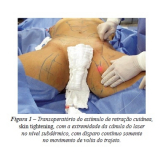

Lipoaspiração a Laser

Você merece a qualidade e comprometimento entregues pela equipe deste consultório médico e se neste momento está à procura de uma equipe que realize lipoaspiração a laser saiba que a FF Cirurgia Plástica disponibiliza de imediato este serviço para você!

Lipoaspiração a laser: atendimento eficiente e com qualidade que você sempre buscou!

Neste consultório médico você encontrará profissionais eficientes e com experiência de excelência. Usufrua de bom atendimento, através dos melhores preços do mercado e de assistência especializada sempre à sua disposição! Leve as suas dúvidas, converse com a equipe da FF Cirurgia Plástica. Contrate bons serviços e sinta-se mais seguro para cuidar da saúde.